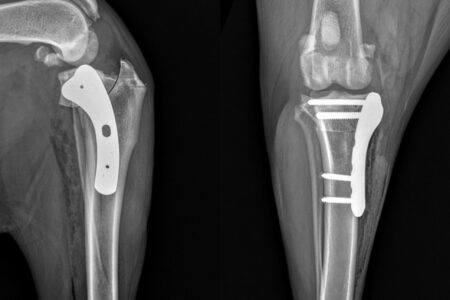

Na RedeVet 24 horas realizamos atendimentos ortopédicos com uma equipe extremamente qualificada para o diagnóstico e tratamento das afecções ortopédicas. Além de tratamentos específicos em relação a fraturas e luxações, aqui você também encontra tratamentos mais específicos como: osteotomia de nivelamento do platô tibial (TPLO), transposição da tuberosidade tibial (TTT), diagnóstico e tratamento da displasia do quadril, diagnóstico e tratamento da displasia do cotovelo, etc.